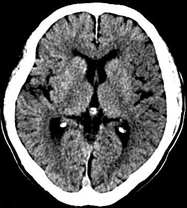

如上圖所示,相鄰的三張軸位圖像未見明顯異常,根據傳統軸位圖像很難得到準確的臨床診斷。

同一病人利用容積數據進行三維處理后,高品質MPR和三維圖像上則清晰顯示了縱向排列的腹腔干與腸系膜上動脈相鄰近,血管發生變 異,近端血管閉塞,為臨床提供了精確的診斷信息。